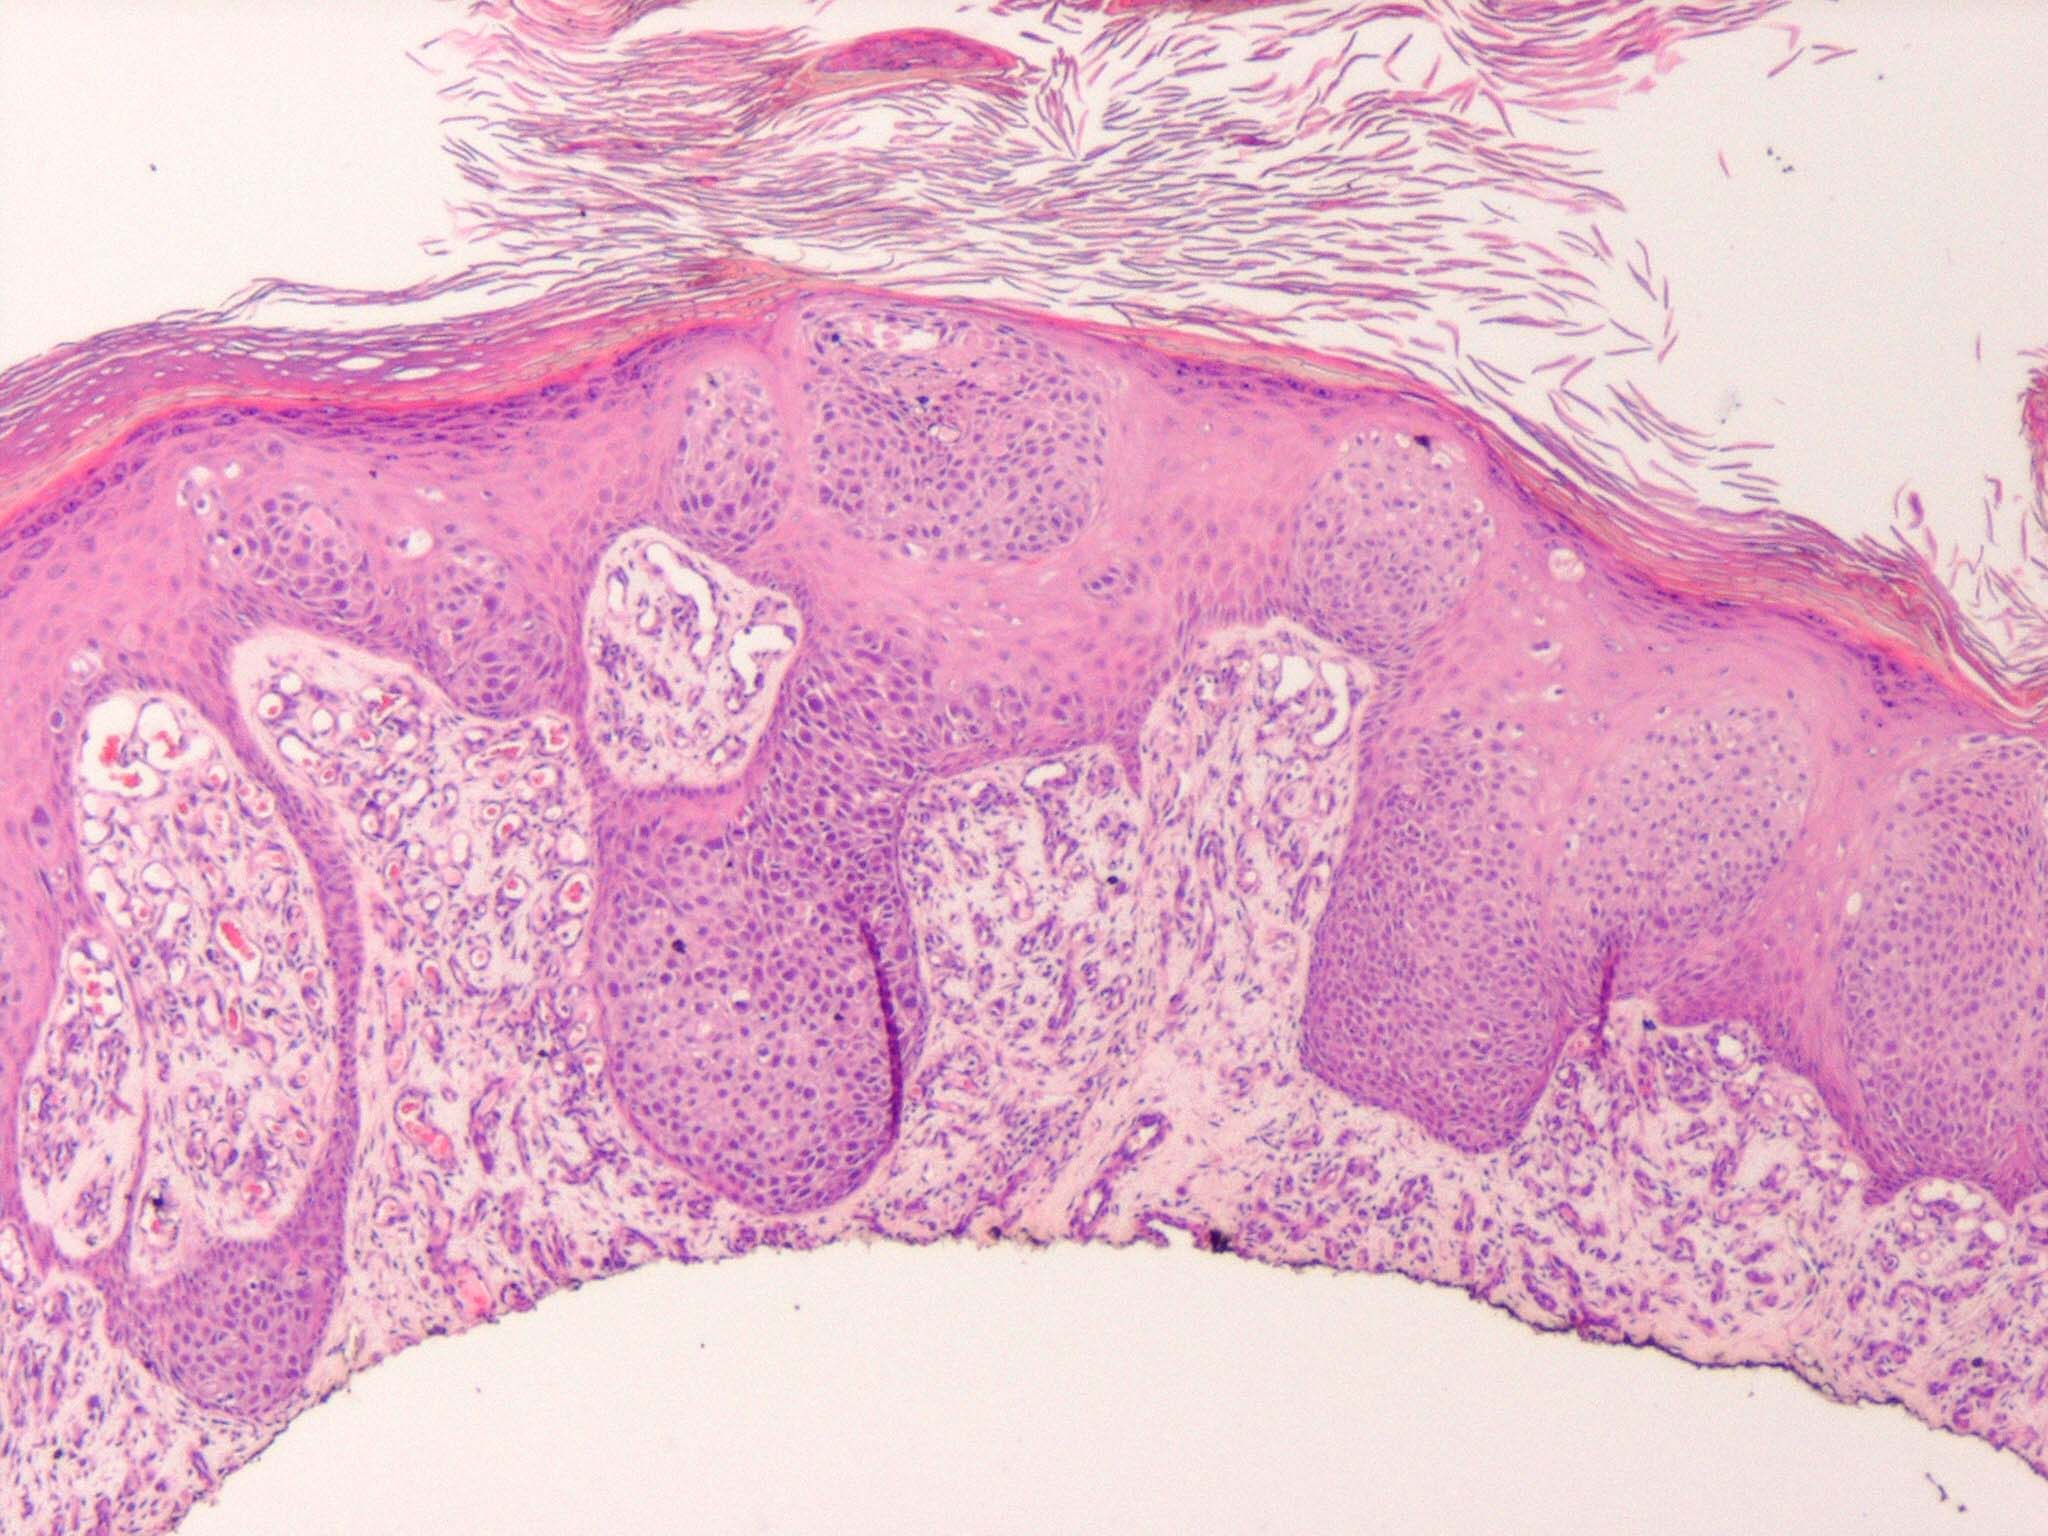

Intraepidermal eccrine carcinoma = الكارسينوما الناتحة داخل البشرة

OLYMPUS DIGITAL CAMERA